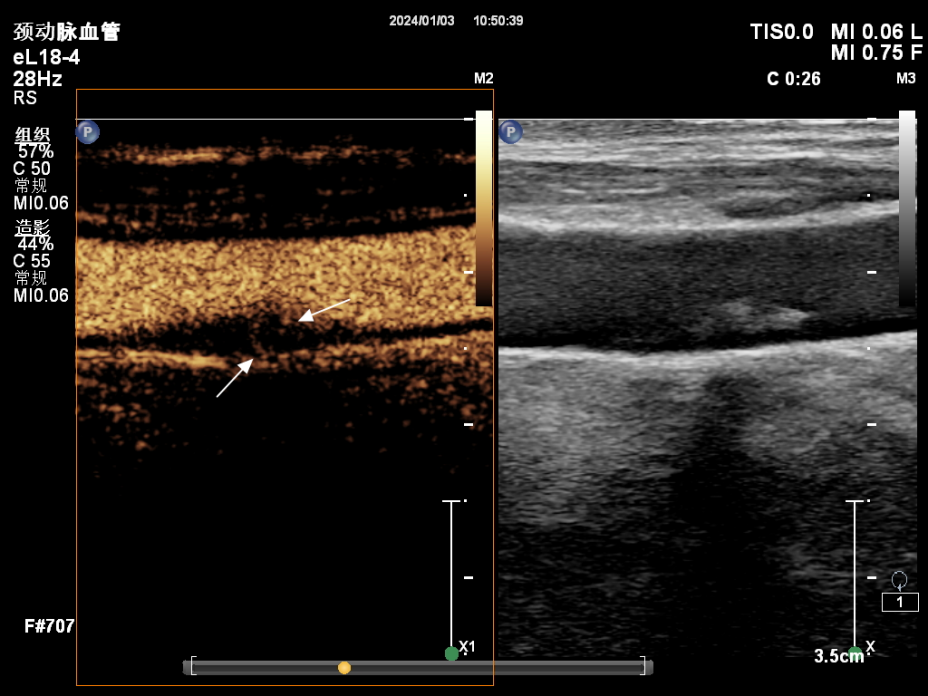

超声造影是在常规超声检查的基础上,通过静脉注射超声造影剂,增强对比作用,无创性评价斑块的稳定性及急性脑血管疾病的发生风险,弥补了常规超声的不足,是一种诊断颈动脉易损斑块的安全、有效、无创的检查方法。

我们把粥样硬化斑块大致分为稳定型和不稳定型两种类型。稳定型斑块新生血管少,纤维帽较厚,脂质池较小,因而通常不会引起明显的临床症状; 不稳定性斑块---易损斑块,指的是那些具有较高风险发生破裂、产生血栓或迅速进展的斑块,易损斑块结局:斑块破裂和(或)血栓形成;危害就是与卒中的发生密切相关。

新生血管是衡量斑块稳定性的重要指标之一,它的密度越大,代表着稳定性越差,就越容易破裂而脱落,碎片游走到全身各处,跑到哪里破坏到哪里。

05颈动脉的超声造影报告怎么看?

我们把颈动脉斑块造影分做4级:I~IV级依此显示新生血管从无到有,逐步增多。其中I~II级为稳定斑块,II~IV级为易损斑块。我们可以借助超声造影清晰地显示斑块的表面溃疡,整体形态等结构; 还能清晰显示动脉管腔狭窄的位置以及是否合并闭塞,指导临床进一步干预及评估干预效果。